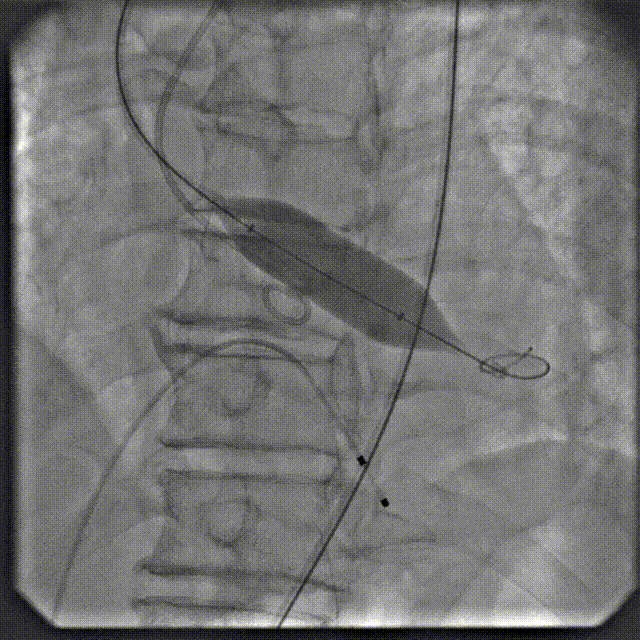

手术过程

根部造影

跨瓣

球扩

定位

释放后造影

后扩

最终造影

术后复查造影示瓣膜位置满意,形态良好,冠脉显影良好;TTE示轻中度瓣周漏,少量心包积液;排除入路血管问题,手术圆满成功。